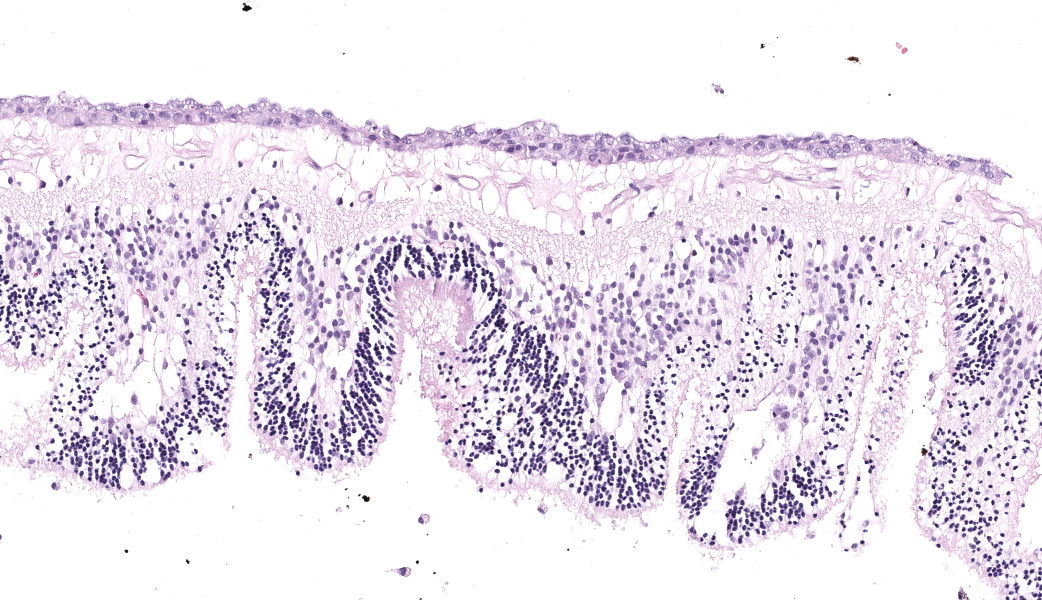

Eye: Overlying the corneal endothelium, anterior and posterior iris, portions of the lens epithelium, and the inner surface of the retina, as well as effacing and replacing the ciliary body, and occluding the drainage angle is an unencapsulated, densely cellular, infiltrative, neoplasm composed of epithelial cells arranged in broad dense cords on a moderate fibrovascular stroma. Neoplastic cells are polygonal with distinct cell borders, pronounced intercellular bridging, a moderate amount of pale eosinophilic cytoplasm, and irregularly round to vesiculate nuclei, with up to three distinct nucleoli. Anisocytosis and anisokaryosis is moderate. The mitotic rate is high with up to 12 mitotic figures per ten 40x HPF. Multifocally, neoplastic cells exhibit squamous differentiation. Near the optic nerve, the neoplastic cells invade the vascular and fibrous tunics, elevating and dissecting beneath the retinal pigment epithelium under a detached and coiled degenerate retina. At the caudal interior surface of the globe, there are numerous neutrophils admixed with abundant eosinophilic cellular and karyorrhectic debris and neoplastic cells infiltrate into the retinal vasculature.Contributor's Morphologic Diagnoses:

This case contributor gives a thorough review of intraocular neoplasms in cats, touching on many major points of discussion during review of this case. Conference participants were readily able to reach a diagnosis of metastatic carcinoma, but not all were convinced that this was a metastatic squamous cell carcinoma (SCC) due to the lack of dyskeratosis within neoplastic epithelial cells, coupled with the lack of a primary mass found during workup. The prominent intercellular bridging between the neoplastic cells was noted by all, which can be a major feature of SCC; and squamous cell carcinomas are common tumors of the feline head; however other participants felt strongly that they could not rule out a carcinoma of other origin based on histology alone. For this reason, a morphologic diagnosis of “metastatic carcinoma” was ultimately favored by participants in this case due to the lack of clear-cut evidence of a squamous cell carcinoma on the H&E.There was no argument to be found on whether this was primary or metastatic, as the histologic evidence was strongly supportive of a metastatic process (i.e., the neoplasm primarily found within the highly vascular choroid and uvea, intravascular neoplastic cell emboli, etc.). The secondary changes in the eye were also discussed and it was concluded that this eye had glaucoma secondary to the neoplasm, evidenced by the retinal ganglion cell degeneration and loss with tapetal sparing, occlusion of the drainage angles by both the neoplasm and inflammation, buphthalmia (enlarged globe, attenuated and degenerative corneal epithelium, scleral thinning), and perivascular edema of the aqueous veins that drain the trabecular meshwork of the drainage angle.